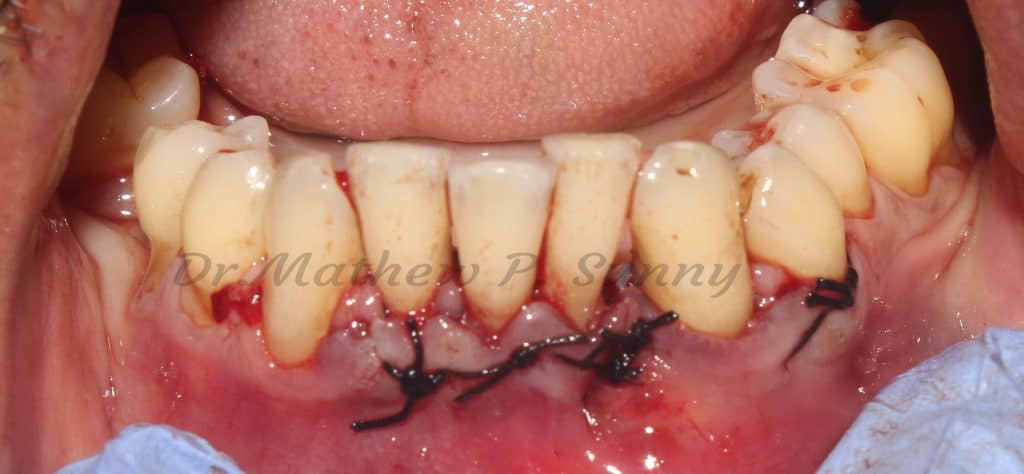

sling and simple interupted sutured used to close the flap.. patient put on antibiotics, analgesics and chlorhexidine..

healing at 1 week at suture removal.. note the resolution of the abscess..